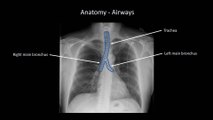

How to Interpret a Chest X-Ray (Lesson 7 - Diffuse Lung Processes)